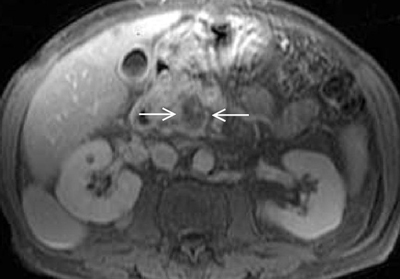

Pankreas kanserinin tanısı

Eskiden pankreas kanseri tanısı koymak oldukça güçtü. Doktorlar görerek veya muayene ederek bu tanıyı koyamazlar. Pankreas kanseri şüphesi olan hastalara önce görüntüleme yöntemleri (MR, CT, Ultrasonografi) yapılır ve ilave tetkikler istenir. Günümüzde en güvenilir yöntem kaliteli yapılmış Bilgisayarlı Tomografi (BT) ve gerektiğinde Manyetik Rözonans (MR) görüntüleme sistemleridir.